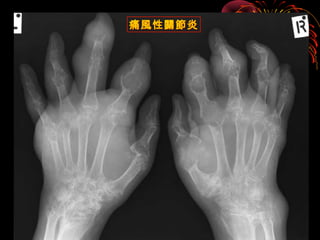

痛風性關節炎